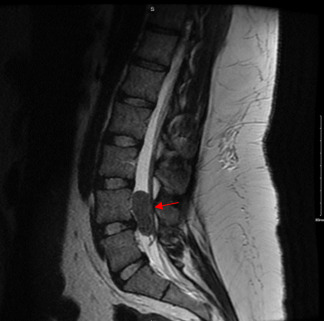

On examination, the patient demonstrated mild diffuse tenderness in the lumbar region. Neurologic exam including gait and reflexes was within normal limits. Given the chronicity of her symptoms, further imaging was indicated to evaluate for an underlying etiology of her pain. The patient underwent an MRI of the lumbar spine, which revealed a well-circumscribed mass noted in the spinal canal at the level of L4-L5. This mass occupied the entire spinal canal and compressed the adjacent neural structures. The lesion appeared intradural, and initial differential diagnosis included meningioma, schwannoma, ependymoma or other primary central nervous system (CNS) neoplasm. Additional cross-sectional imaging of the chest, abdomen, and pelvis did not show evidence of metastasis.

Primary spinal cord tumors account for only 2-4% of all primary CNS tumors.4 Spinal meningiomas typically occur in patients over age 70, with a four-fold greater incidence in women as compared to men.5 Clear cell meningiomas are a rare CNS tumor that may present with atypical symptoms when located in less common areas. The majority of clear cell meningiomas are intracranial, with only a small margin being found in the spine.6 Clinical presentation varies based on location of tumor and on the depth of the tumor within the cord. Clear cell meningiomas in the spine may produce neurologic deficits and pain due to local compression of the spinal cord, vessels, nerves, and adjacent structures.4 Overall, the most common presenting symptoms of spinal meningiomas are motor dysfunction (92%), sensory disturbance (78%), pain (76%), gait disturbance (42%), and bowel or bladder dysfunction (28%).6 MRI often shows a well demarcated, intradural, homogeneously enhancing mass. Surgical resection is the gold standard treatment for spinal meningiomas, often alleviating symptoms with minimal risk of recurrence postoperatively.7 Radiation therapy is a consideration for higher grade tumors or in patients unable to undergo surgery, though the role of non-surgical therapies is variable.